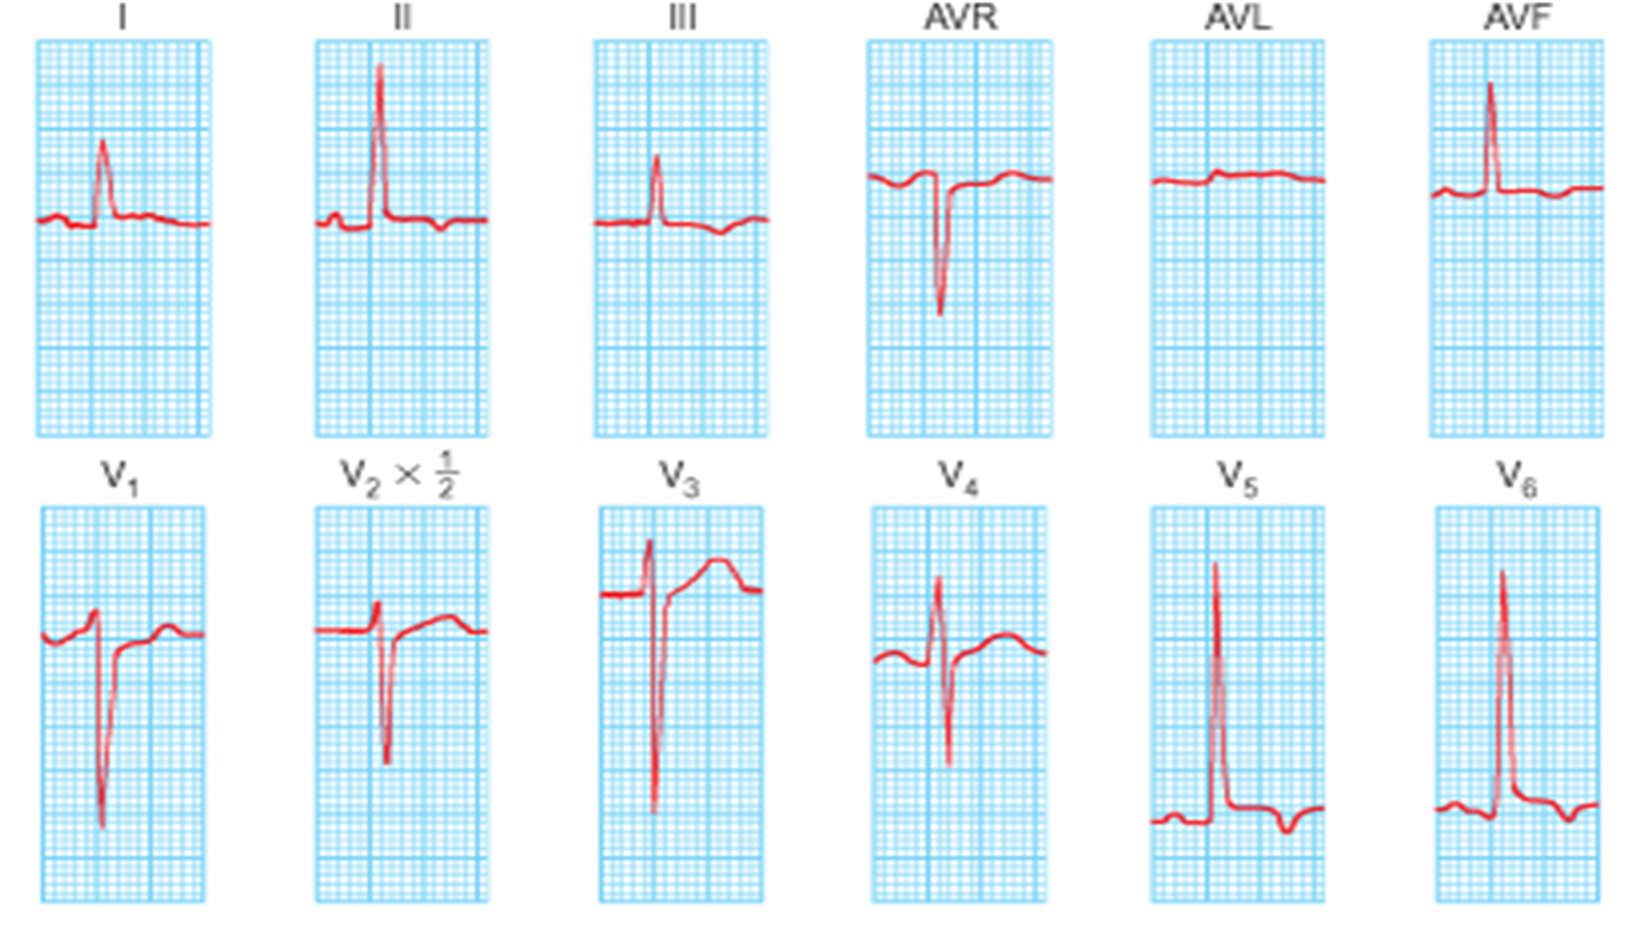

ECG:

- Left ventricular hypertrophy with strain pattern, left axis deviation.

V2 + V6 Ventricular hypertrophy squares cc

V2 + V6 Ventricular hypertrophy squares cc